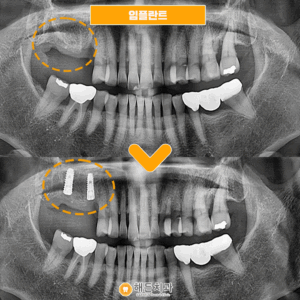

해든치과 임플란트 환자분의 간식선물🥨

안녕하세요~ 해든치과입니다 임플란트 치료분인 환자분께서 치료 전 통증과 불편함이 계속 있었지만 치과에 대한 두려움 때문에 한동안 참고 지내시다가 내원해 주셨습니다 그동안 치과에 대한 기억이 좋지않아 차마 발걸음이 떨어지지 않았는데 막상 치료받아보니 걱정이 무색하게 안아프게잘 치료해주셔서 너무 감사하시다며, 치과 공포증이 다 사라졌다시며 간식을 선물해주셨어요! 예쁘게 생긴 도넛이 맛도 얼마나 좋았는지 ㅠㅠ 더보기…